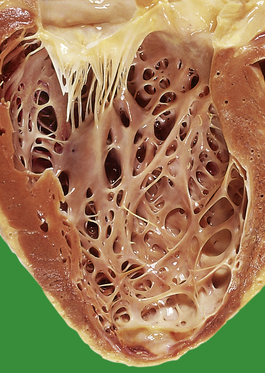

Benign (essential) hypertension

The increased peripheral vascular resistance and cardiac workload associated with hypertension produce left ventricular hypertrophy. During life this can be detected electrocardiographically, and at postmortem there is often substantial concentric thickening of the left ventricle. With the development of congestive cardiac failure, the hypertrophy can be obscured by left ventricular dilatation. Some patients with hypertension also have coronary arterial atherosclerosis and evidence of consequent ischaemic heart disease.